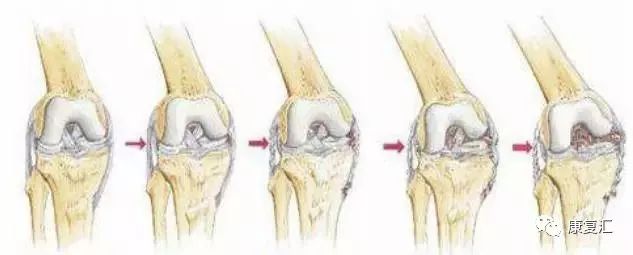

膝关节骨性关节炎( knee osteoarthritis,KOA) 又称为膝关节增生性关节炎、退行性骨关节病等,是一种多发的慢性进行性骨关节疾病。临床表现为膝关节出现弹响、肿胀、疼痛、活动受限等一系列症状。

多发于中老年,发病率随年龄而增加,女性多于男性。60岁以上的人群中患病率可达50%,75岁以上的人群中则达80%。该病致残率可高达53%。流行病学调查表明,55岁以上的老年人的发病率为44%~70%。

在发病机制方面,与遗传、性别、年龄、肥胖、创伤以及炎症有关,膝关节不稳定和力线异常是导致 KOA 的主要生物力学因素。